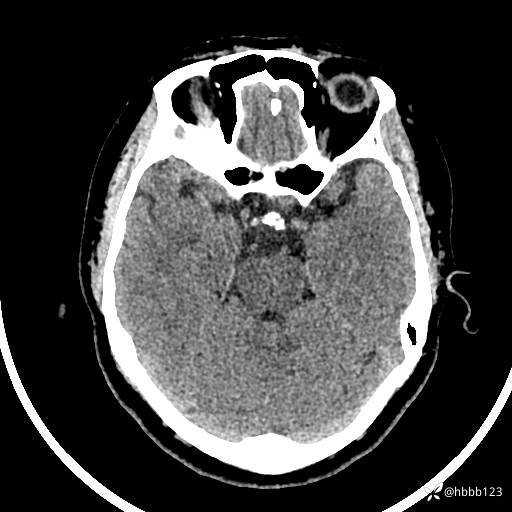

颅脑CT平扫: